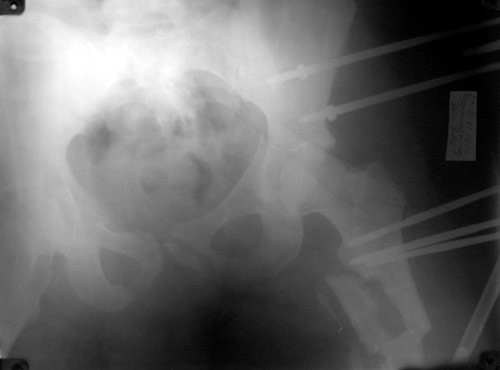

Таз

Бедро

То, что получилось в приложении. Стоит ли дальше тянуть головку винтами или низводить проксимальный отломок по оси?

Уважаемый Борис! Я не имел возможности ознакомиться с рентгенологической картиной сразу после травмы. Имею картинку на данный момент (Ваше приложение). Считаю, что Вы имеете право оставить всё в имеющемся состоянии, но желательна дополнительная дистракция по оси шейки бедренной кости. Далее стабилизировать аппарат. Артроз больному обеспечен, сроки наступления его декомпенсации известны только аллаху.

С> То, что получилось в приложении.

Можно только порадоваться за пациента и врачей, положение отломков значительно улучшилось. Может быть, удастся добиться "вторичной конгруэнтности" даже при сохраняющемся диастазе на уровне перелома. Из того, что видно - стержней в тазу маловато, лучше бы зацепиться за гребни подвздошных костей (по 3-4 стержня), тогда можно будет пациента и поднять на костыли.

Возможно, и то, и другое. По одной прямой проекции ситуацию не оценить - желательно сделать косые проекции (Judet) левой вертлужной впадины, на которых будет видно, конгруэнтна ли головка со сводом, не надо ли подвинуть ее кпереди или кзади.

По бедру - ось (по одной проекции) и длина восстановлены. Непривычно выглядит стержень с медиальной стороны, мы обычно обходимся только

наружной полуокружностью бедра. Если аппарат здесь предполагается как окончательный фиксатор - похоже, это надолго...

На первый взгляд репозиция вертлужной впадины не плохая, однако следует сделать проекционные снимки по Judet, а вот аппрат конечно подкачал, да и больного жалко. Былобы красиво сейчас после рентген-контроля перкутанно ппровести стягивающие винты через перелом вертлужной впадины из подвздошной в лобковую и из седалищной в подвздошную. А бедро заштифтовать, а потом снять аппарат и отпустить больного, передний отдел возможно фиксировать АВФ.